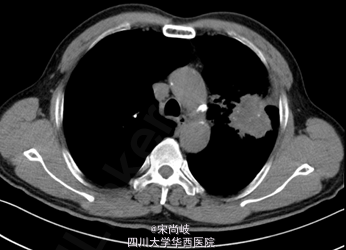

胸廓桶状,双肺呼吸音过清。胸部CT提示双肺慢支炎肺气肿表现,左肺上叶见4.9*4.0CM软组织肿块。

诊断为:左上肺包块。全麻下行剖胸探查+左肺上叶肿物取活检术,术中见胸内淡黄色积液50ml, 轻度粘连,胸膜有种植; 肿块位于肺门部及上下肺叶,约8*7*7cm大小,有脏层胸膜皱缩、有侵犯壁层胸膜;肿瘤距隆突<2cm,侵及纵隔胸膜,心包;淋巴结肿大及侵犯情况:7组,10组,11组淋巴结肿大,质硬,与周围组织紧密粘连;术中冰冻果:(左上肺肿物)倾向非小细胞型肺癌,术中特殊情况:左上肺肿物侵入左下肺及左肺门部,质硬,活动度差,周围淋巴结肿大,质硬,与肿物紧密粘连,无法分离。术中过程顺利,术中出血约50ml,术后安返,给予止痛,抗炎,化痰等治疗。